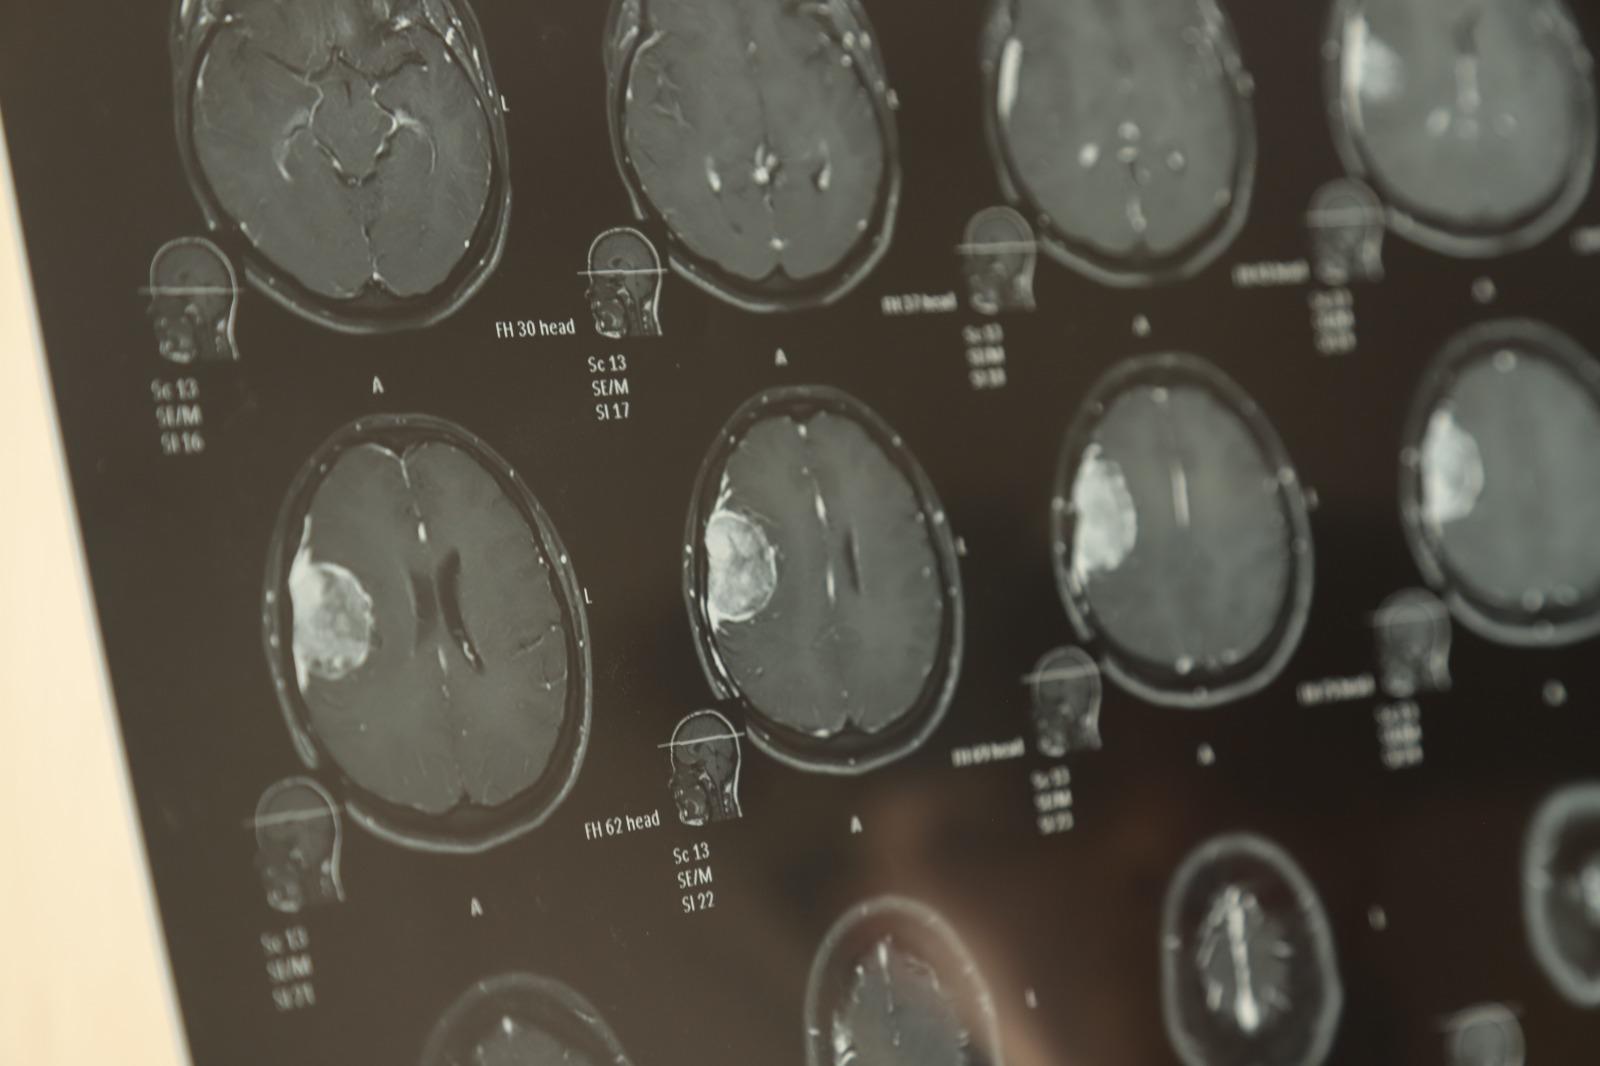

De 36 años, mamá de dos hijas, de 9 y 2 años y medio, Iris Analí narró cómo apenas 18 días antes se enteró de que en su cerebro está alojado un angioma al parecer benigno, que mide 4.3 centímetros por 3 centímetros.

“Con un neurólogo él me mandó hacer una resonancia y arrojó que era un tumor aparentemente benigno, pero ocupo una operación y sí es muy costosa. Me sale en 250 mil pesos”, comentó.

Clamó la ayuda de la ciudadanía con poquito o mucho para poder reunir la cantidad necesaria para ser operada; la cirugía es delicada por la zona donde se encuentra ubicado el tumor que envuelve una vena pegada al hueso y que tendrán que limar para colocar una placa.